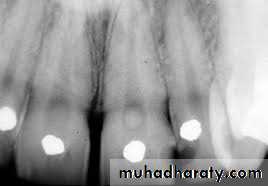

2. Calcifications

In calcific degeneration, part of the pulp tissue is replaced by calcific material. Mainly three types of calcifications are seen in pulp:Dystrophic calcification: occur by deposition of calcium salts in dead or degenerated tissue. The local alkalinity of destroyed tissues attracts the salts.

Diffuse calcification: They are generally observed in root canals. The deposits become long, thin and fibrillar on fusing.

Denticles/pulp stones. These are usually seen in pulp chamber.

Classification

According to location:•Free

• Embedded

• Attached

According to structure:

•True• False

True denticles: It is composed of dentin formed from detached odontoblasts or fragments of Hertwig’s enamel root sheath which stimulate and undifferentiated cells to assume dentinoblastic activity.

False denticles: Here degenerated tissue structures act as nidus for deposition of concentric layers of calcified tissues.